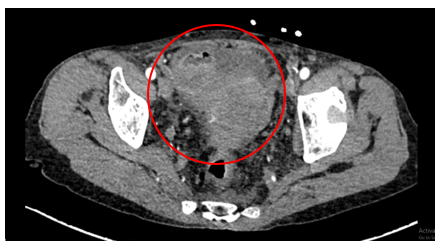

Chụp CT ổ bụng có tiêm thuốc cản quang:

Hình 1: Hình ảnh khối vùng tiểu khung kích thước 52x69mm (vòng tròn đỏ).